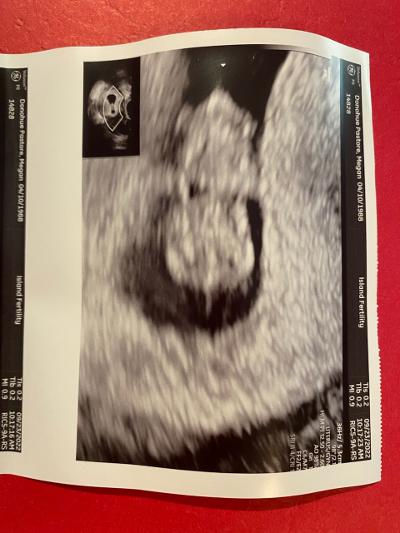

Here is my future grandson or granddaughter:

I think the baby is just all curled up in a ball. I told Michael it is a cute little blob. To me, the head looks like a doll head!